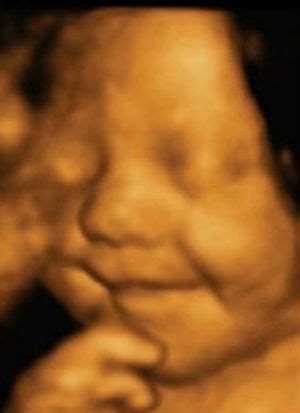

Pastaruosius kelerius metus plačiai kalbama apie 3D ir net 4D vaisiaus echoskopiją. Paklausta, ką reiškia šie skaičiai, gydytoja paaiškina:

„2D - tai įprasta dvimatė echoskopija, kai ultragarso aparato ekrane ar pateiktoje nuotraukoje matomas nespalvotas dvimatis vaizdas. 3D jau leidžia sudaryti erdvinį trimatį vaizdą, kai ekrane galima stebėti ir vaisiaus veido bruožus, 4D - tai iš kelių atskirų 3D vaizdų sudarytas vienas klipas, tarsi filmukas.

Kaip atskira echoskopijos rūšis gali būti išskiriamas ir doplerinis tyrimas, kurio metu galima stebėti tam tikrų sričių vaisiaus kraujotaką“, - sako gydytoja akušerė-ginekologė.